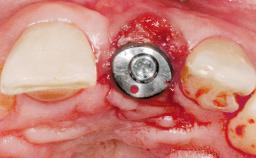

Immediate Placement of an Implant in a Maxillary Right Central Incisor Site

A 30-year-old female patient was referred to the office for the treatment of tooth 11. Her chief concern at the initial visit was to inquire, “Why is my tooth pink?” Upon clinical examination, it was determined that tooth 11 had a previous history of trauma and that the clinical crown had become noticeably pink in color as a result of internal resorption. This diagnosis was confirmed radiographically, indicating a large radiolucency involving the central and distal portions of the clinical crown. It was determined that restoration of this tooth was not possible, and that extraction was indicated. The presence of a mid-line diastema, which the patient wanted to reproduce, directed the treatment plan for tooth replacement utilizing a dental implant.

| Type of Implants | One-Piece|Reduced-Diameter |

| Placement Protocol | Immediate implant placement |

| Tooth Site | Maxillary incisor or canine |

| Socket Morphology | Single-root socket |

| Socket Integrity | Sufficient, with intact bone walls |

| Bone Volume | Sufficient, with intact walls |